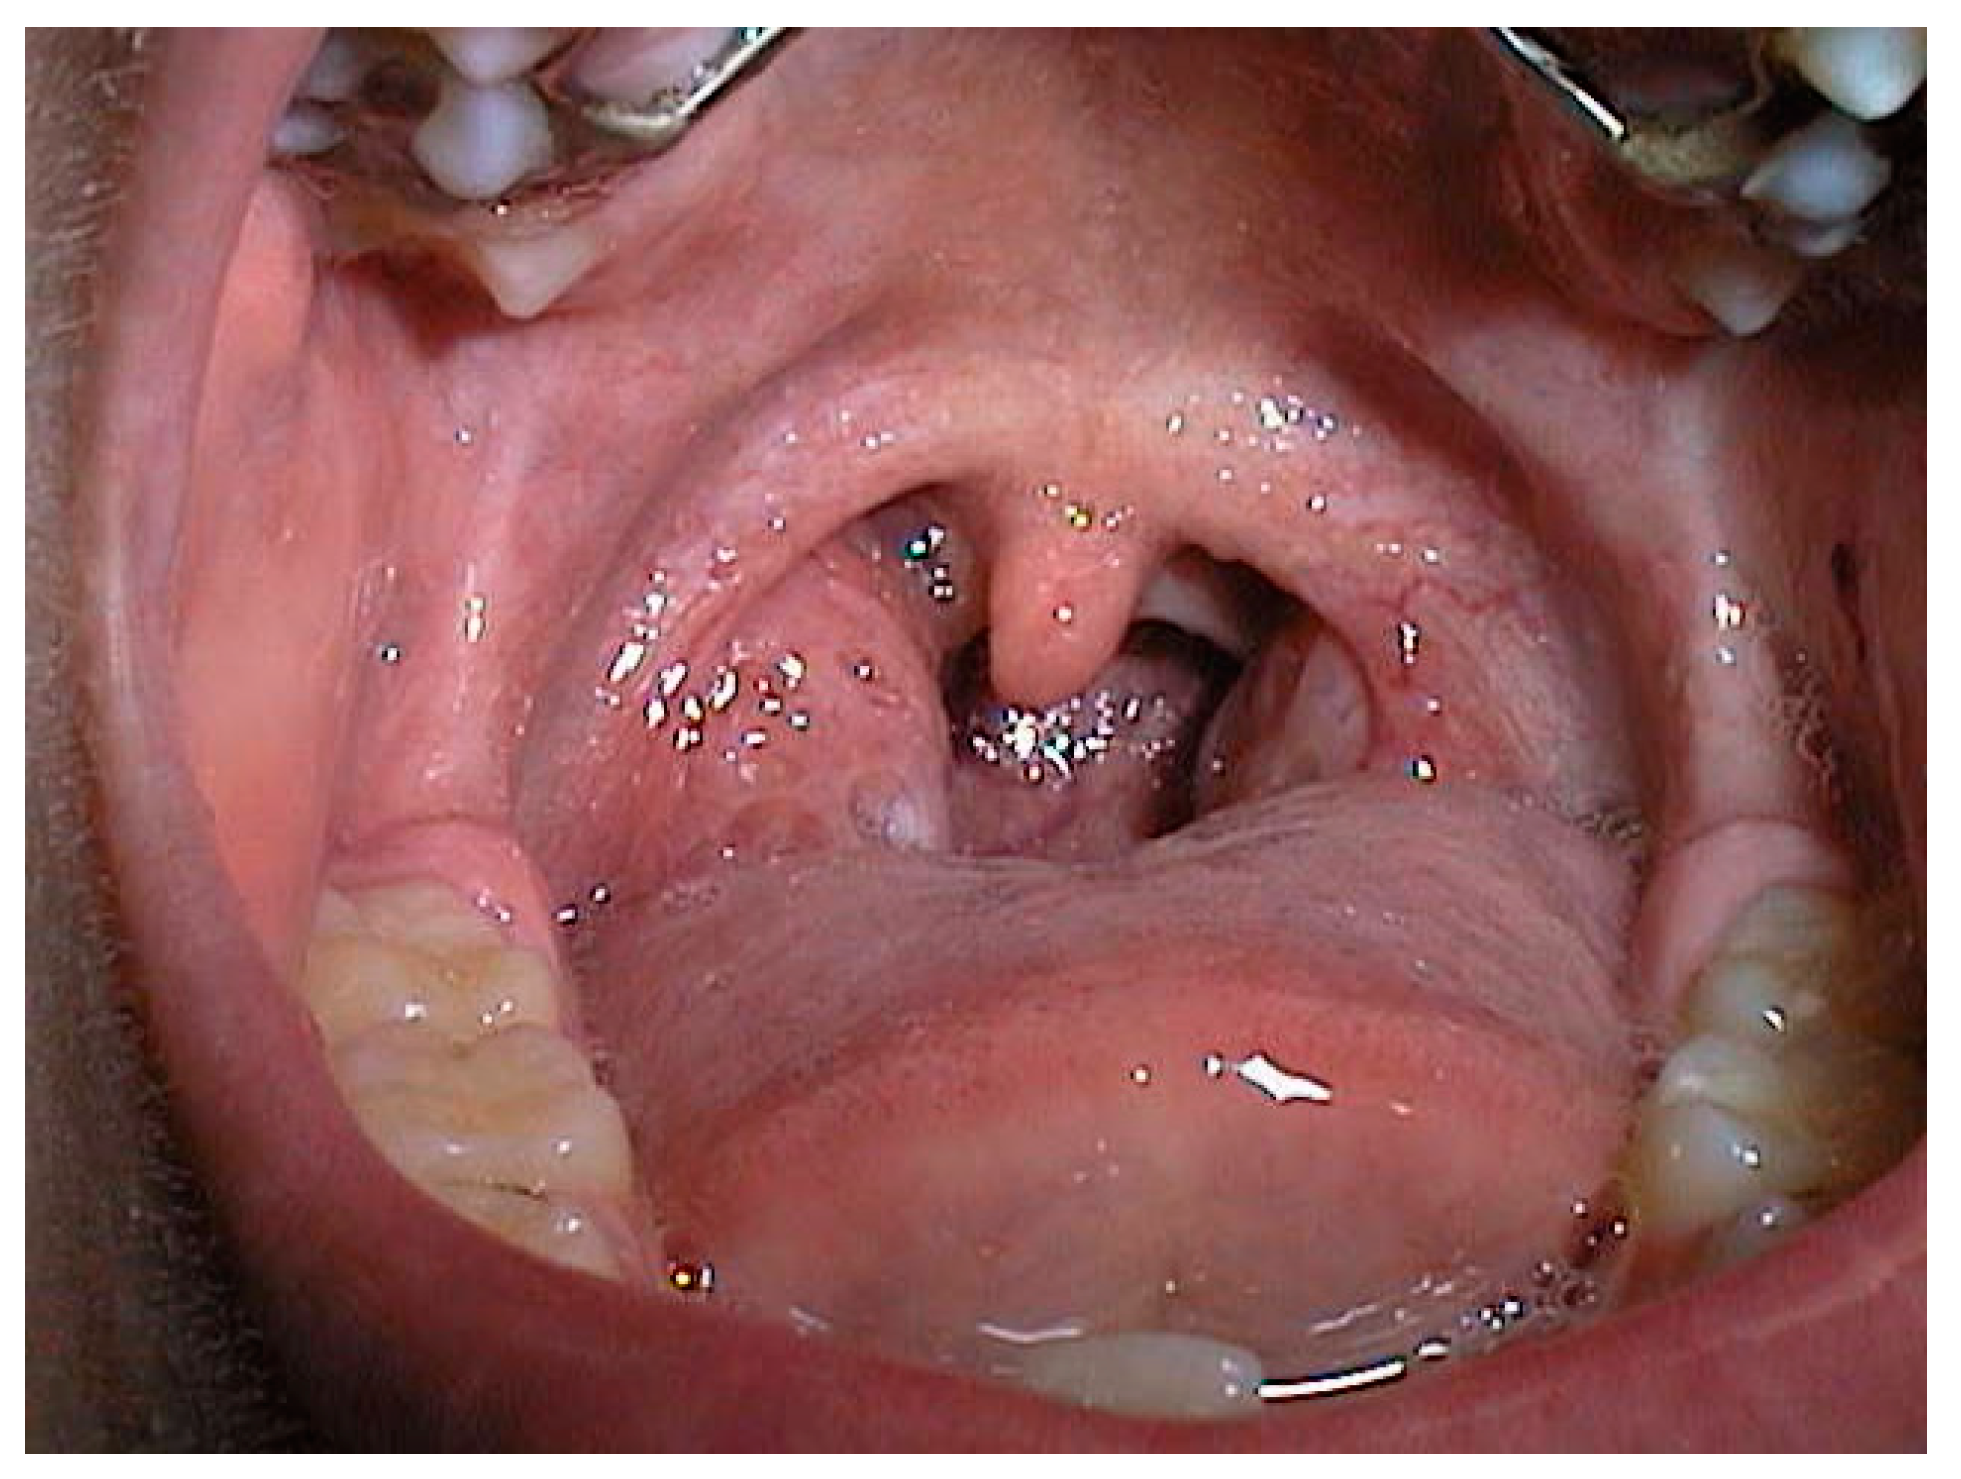

Adenotonsillar hypetrophy contributes to the narrowing of the retro-palatal area, which has the smallest cross-sectional area and is therefore the most frequent site of obstruction, as shown in a 6 years old patient in Figure 1. In particular, children with Grade IV tonsils (kissing tonsils) are very susceptible to developing sleep disorders, due to oropharyngeal narrowing and lateral collapse.

Figure 1.

Grade III tonsil hypertrophy in a 6 year-old child. Courtesy of Professor C. Vicini—Department of Head-Neck Surgery, Otolaryngology, Head-Neck and Oral Surgery Unit, Morgagni Pierantoni Hospital, Forlì, Italy.